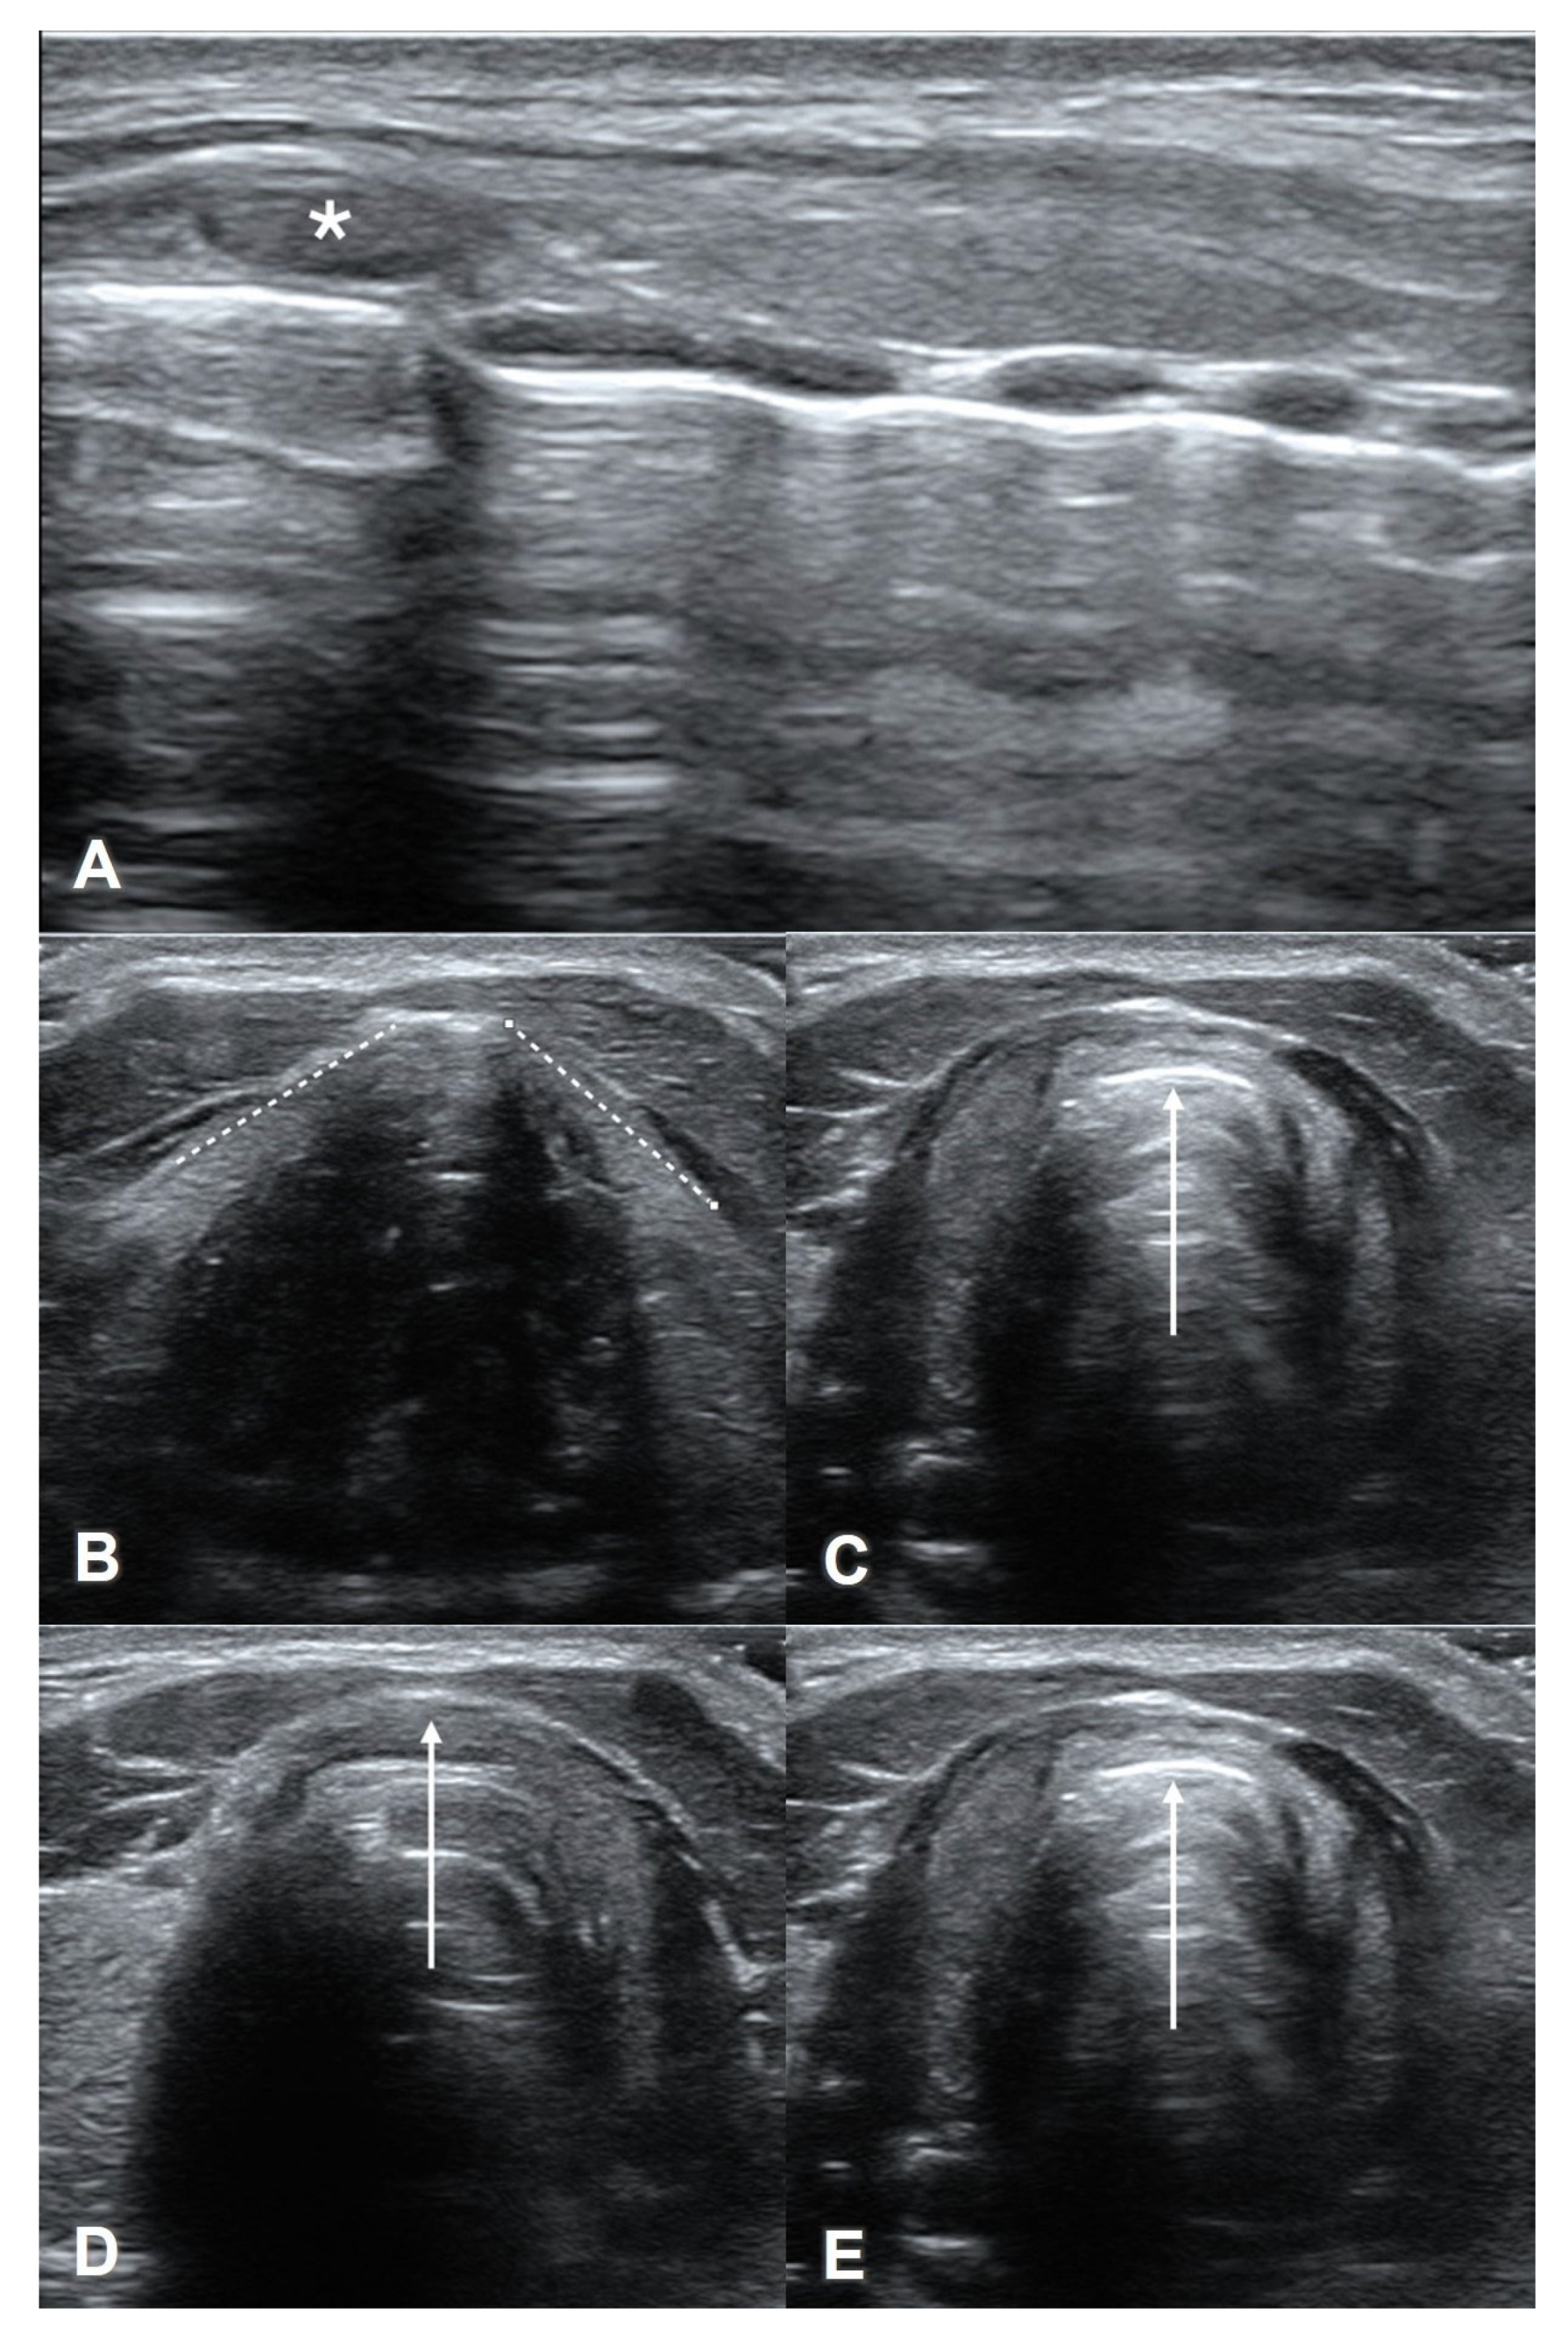

4.3. Thyroid View

8. Preparation for Cricothyrotomy

- Kristensen, M.S.; Teoh, W.H.; Rudolph, S.S. Ultrasonographic identification of the cricothyroid membrane: Best evidence, techniques, and clinical impact. Br. J. Anaesth. 2016, 117 (Suppl. S1), i39–i48. [Google Scholar] [CrossRef] [PubMed]

- Rai, Y.; You-Ten, E.; Zasso, F.; de Castro, C.; Ye, X.Y.; Siddiqui, N. The role of ultrasound in front-of-neck access for cricothyroid membrane identification: A systematic review. J. Crit. Care 2020, 60, 161–168. [Google Scholar] [CrossRef]

- Hung, K.C.; Chen, I.W.; Lin, C.M.; Sun, C.K. Comparison between ultrasound-guided and digital palpation techniques for identification of the cricothyroid membrane: A meta-analysis. Br. J. Anaesth. 2021, 126, e9–e11. [Google Scholar] [CrossRef] [PubMed]

- Kristensen, M.S.; Teoh, W.H.; Rudolph, S.S.; Hesselfeldt, R.; Børglum, J.; Tvede, M.F. A randomised cross-over comparison of the transverse and longitudinal techniques for ultrasound-guided identification of the cricothyroid membrane in morbidly obese subjects. Anaesthesia 2016, 71, 675–683. [Google Scholar] [CrossRef]

- Nicholls, S.E.; Sweeney, T.W.; Ferre, R.M.; Strout, T.D. Bedside sonography by emergency physicians for the rapid identification of landmarks relevant to cricothyrotomy. Am. J. Emerg. Med. 2008, 26, 852–856. [Google Scholar] [CrossRef]